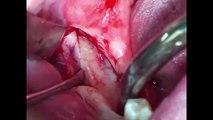

man unterscheidet offene oder geschlossene knochendehnung. zum geschlossenem bone spreading findet ihr hier ein video https://dai.ly/x7tcm84 generell findet ihr fortbildungsvideos in unserer playlist https://www.dailymotion.com/playlist/x6642 sollte ein video / thema nicht dabei sein, dann bitte einfach schreiben und ich werde es ehemöglichst abarbeiten. geschlossenes bonespreading ist immer der offenen variante vor zu ziehen, denn die blutversorgung des knochens bleibt erhalten. nur bei extremen spitzkamm wie in diesem fall ist eine offene vor zu ziehen.